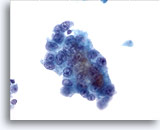

画像 3

肝FNA – 良性肝細胞

核はわずかに大小不同であり、反応性変化を来した肝細胞に典型的な低N/C比を示します。微小な細胞質空胞および細胞質内色素がみられます。

60倍

画像 3

肝FNA – 良性肝細胞

核はわずかに大小不同であり、反応性変化を来した肝細胞に典型的な低N/C比を示します。微小な細胞質空胞および細胞質内色素がみられます。

60倍